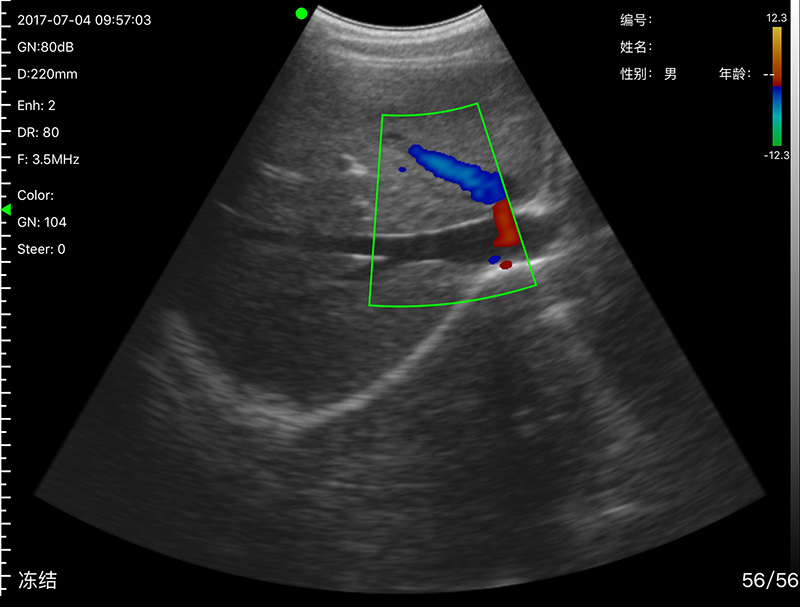

• 探头频率:3.2/5.0MHz

• 扫描深度:90/160/220/305mm,可调

• 显示模式:B、B/M、Color、PW、PDI